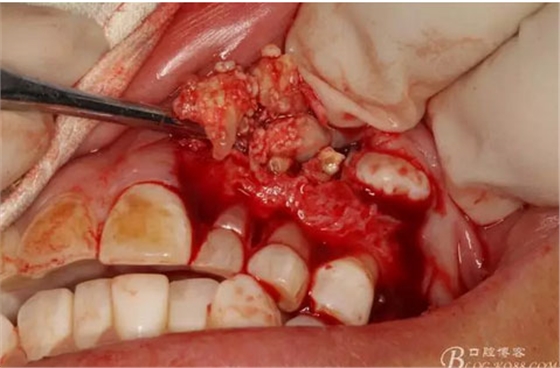

圖15.剝離出來的多個成型小牙齒及致密鈣化物。

圖16.形態(tài)各異的小牙齒。

圖17.呼之欲出的巨大牙瘤組織。